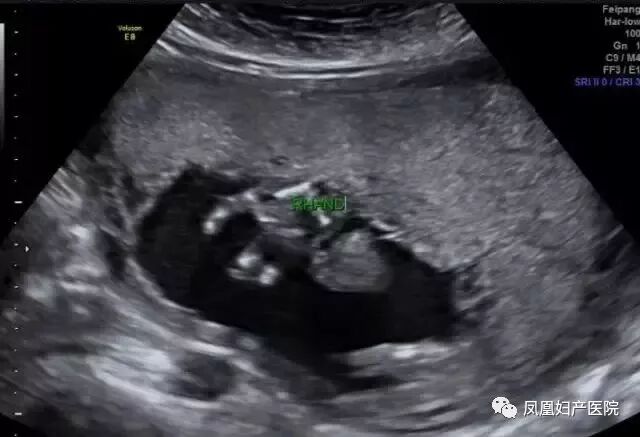

去年一位40岁的二胎妈妈在一次常规的产检中,发现胎儿下肢是两个大腿骨, 并行排列 ,小腿骨好像有点交叉 。正常胎儿的下肢是不停地在妈妈肚子里动的, 呈现一个外八字,后来确诊为美人鱼综合症。因为多数患病的新生儿出生后,只能存活几个小时,就算活下来,也要接受多次手术治疗。

(右侧缺指)